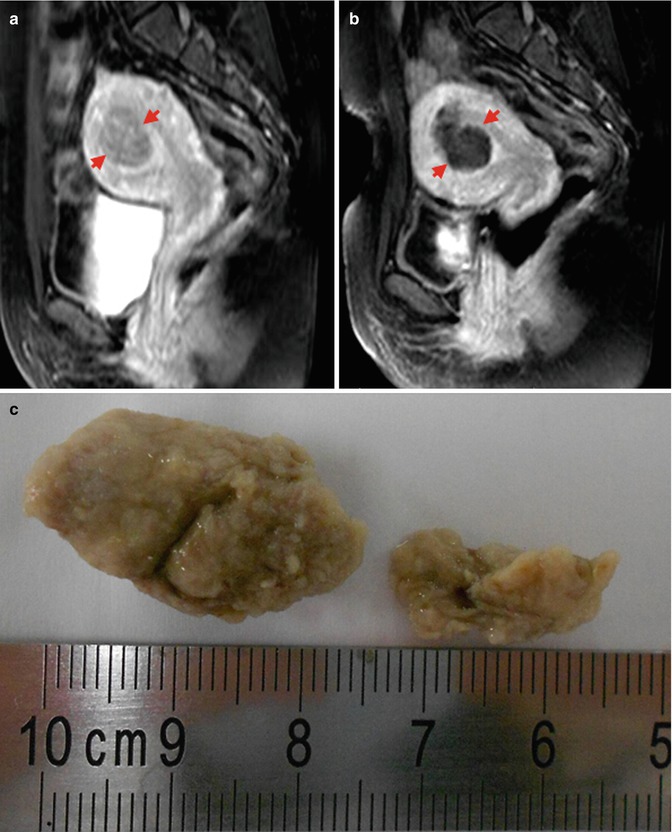

Mri Of The Pelvis A Necrotic 8 2 Cm Subserosal Fibroid Arrow B Download Scientific Diagram

www.researchgate.net